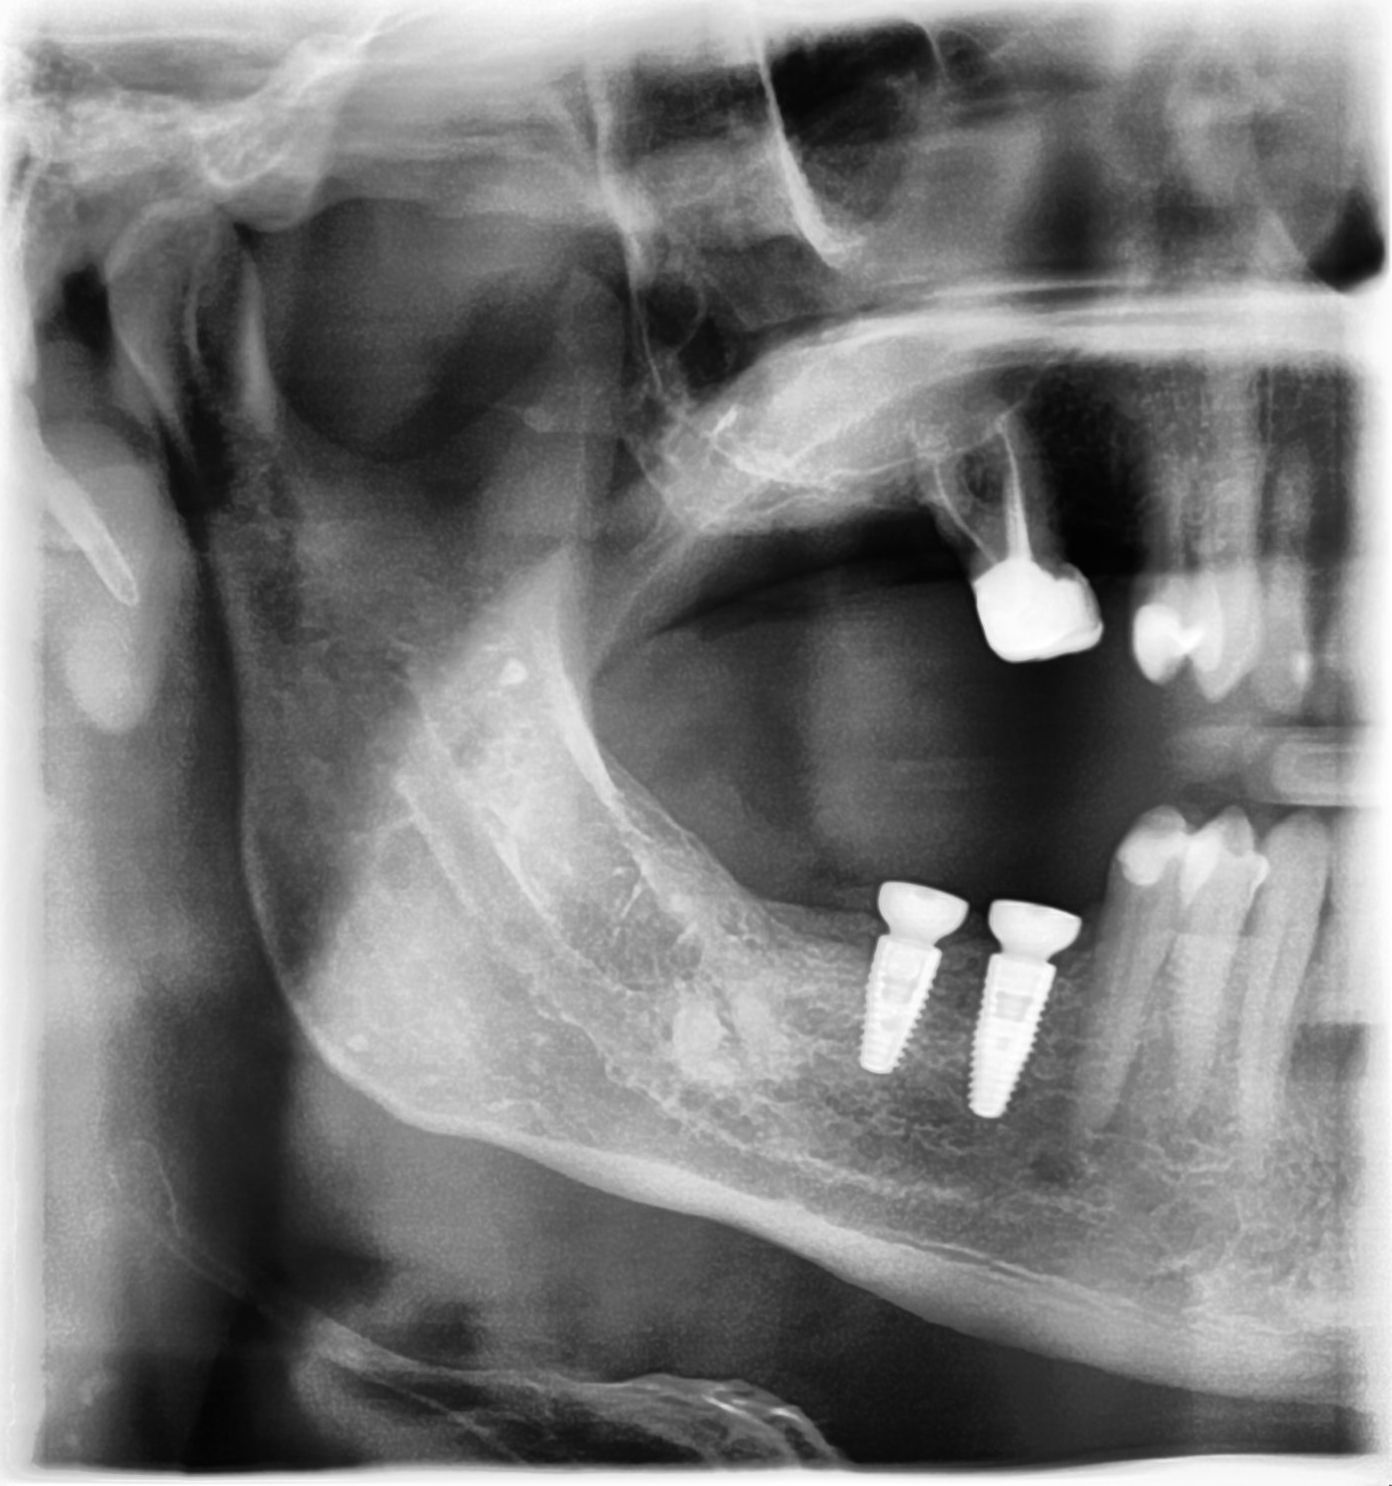

21/28 - X-ray scan of the augmented ridge after implantationThree-dimensional augmentation with maxgraft® cortico - Dr. R. Würdinger